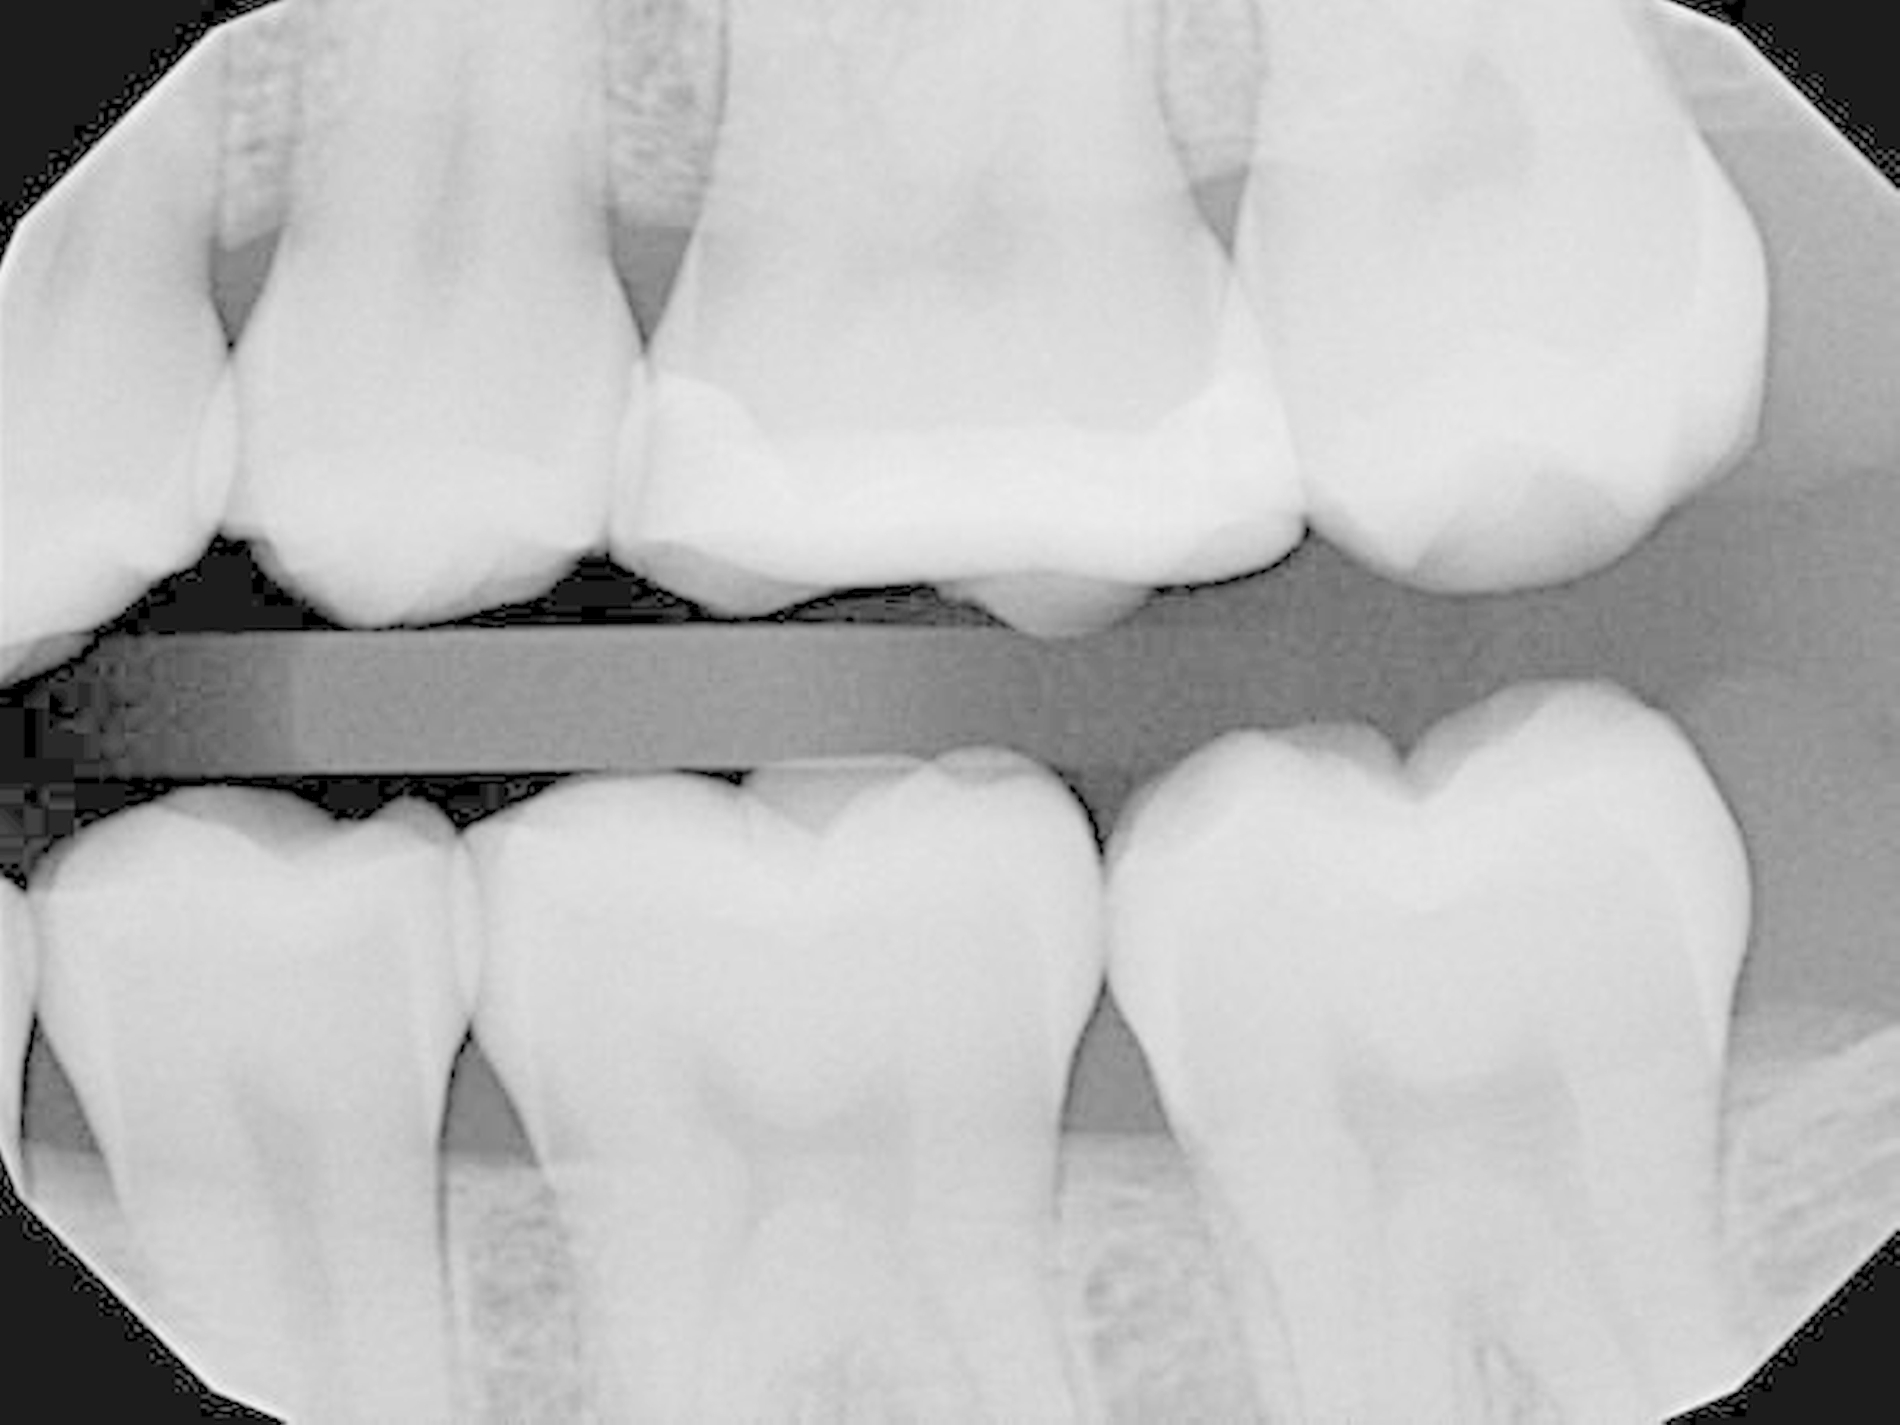

Die 20-jährige Patientin stellte sich zusammen mit ihrer Mutter in der zahnärztlichen Praxisklinik mit Beschwerden an Zahn 26 vor (Abbildung 1). Es zeigte sich ein generell sehr gut gepflegtes Gebiss mit kleinen Füllungen, die eher einer erweiterten Fissurenversiegelung entsprachen. Lediglich an Zahn 26 imponierte ein großes mehrflächiges Goldinlay, das im Prinzip einer Gold-Teilkrone entsprach.

Abbildung 7 zeigt die in der Recall-Sitzung angefertigte Routine-Bissflügelaufnahme, aus der die geringe vertikale Dimensionierung der Versorgung gut erkennbar ist. Die Patientin war mit dieser Neuversorgungsvariante hochzufrieden. Eine Neuversorgung mit einer indirekten Restauration erscheint somit zunächst nicht erforderlich. Auf diese Weise konnte der Zahn mit (im Vergleich zu den angedachten indirekten Restaurationsvarianten) vergleichbar geringem Aufwand zahnhartsubstanzschonend neu versorgt werden.